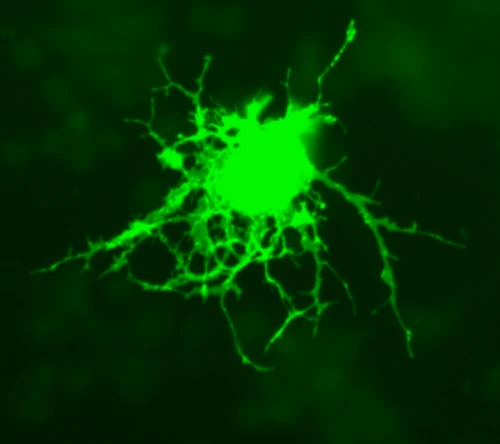

그럼 이런 결과는 어떤 차이에 의해서 일어난 것일까요? 논문의 저자는 희소돌기아교세포(Oligodendrocyte)의 회복이 도움을 주었다고 합니다.

Oligodendrocyte.png?type=w2

희소돌기아교세포는 이렇게 생겼습니다.

희소돌기아교세포의 기능은 CNS의 axon에서 절연기능을 합니다. 신경에 절연을 해서 도약전도를 할 수 있도록 합니다. 즉, 신경기능에 아주 중요한 역활을 합니다.

우리가 일반적으로 알고 있는 것은 Schwann cell이지요. 말초신경에서 myelin sheath를 만드는 기능을 담당합니다. 그런데 희소돌기아교세포의 경우 CNS에서 myelin sheath를 만드는 중요성이 있습니다. 그리고 Schwann cell의 경우 한 세포가 하나의 myelin sheath를 만드는 것에 비교해서, 희소돌기아교세포의 경우 총 50개까지 만들 수 있다고 하네요. 결론은 신경의 회복을 촉진시키는데 도움을 주는 중요한 세포입니다.